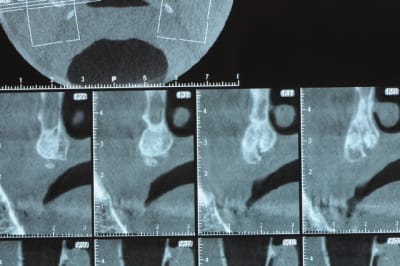

un cas pour PXAV.

ça c'est le domaine de pxav.

qu'en penses tu ?

j'ai besoin de 4 implants au maxillaire pour faire tenir son complet.

dans la zone postérieur, pas de problème, mais devant, c'est une autre histoire.

Non sans décorner, superbe cas de début pour expansion, bone splitting et tout et tout.

la corticale a l'air tiptop, par contre en cas d'expansion il faut eventuellemnt augmenter le nombre d'implant à 6 pour compenser eventuellement le manque d'epaisseur 'avis personnel)